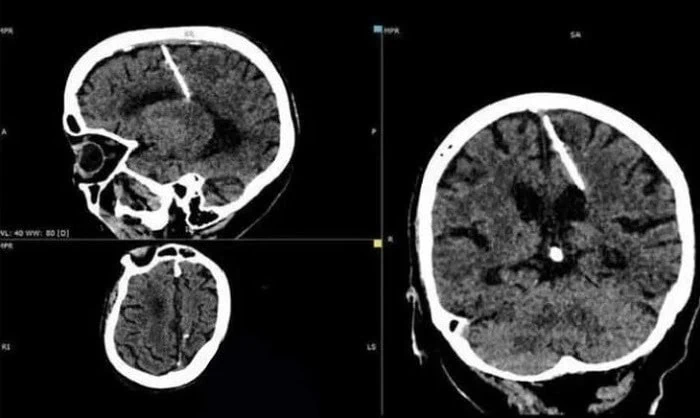

پس از انجام سی تی اسکن، یک زن 80 ساله از منطقه ساخالین روسیه متوجه شد که یک سوزن فلزی 3 سانتی متری در سمت چپ مغزش فرو رفته است. عکس هایی از نتایج سی تی اسکن این زن به تازگی توسط وزارت بهداشت ساخالین همراه با توضیحات تکان دهنده منتشر شده است که در واقع همین توضیحات دلیل وایرال شدن این خبر شد که جزئیاتش را در بخش سرگرمی نمناک میخوانید.

با در نظر گرفتن سن این زن، پزشکان بر این باورند که این سوزن توسط والدین خودش و بلافاصله پس از تولد او وارد مغز او شده است. هر چقدر هم که تکان دهنده به نظر برسد، چنین اقداماتی در روسیه جنگ زده غیرمعمول نبود.

والدینی که توانایی پرداخت هزینه مراقبت از نوزادان خود را در شرایط سخت جنگی نداشتند، سوزن های نازکی را از طریق فونتانل - شکافی در جمجمه که به تدریج با رشد کودک بسته می شود - وارد مغز نوزاد میکردند تا آنها را بکشند و حالا این پیرزن پس از 80 سال متوجه شد که از مرگ نجات یافته تا ثابت کند که مرگ و زندگی تنها دست خدواند مهربان است و بس.

جالب اینجاست طی این سالها، این پیرزن خوش شانس حتی تجربه یک سردرد ساده را هم نداشته که علتی باشد برای مراجعه به پزشک و عکسبرداری و....